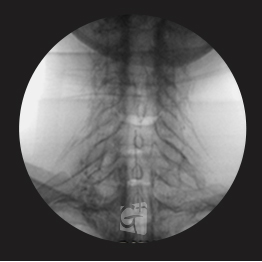

요추 선택적 신경치료

요추 5번에서 시행된 선택적 신경치료 약물이 신경근과 추가공 안쪽으로 잘 퍼지는 모습